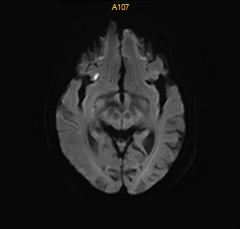

术后DWI:磁共振见少许新鲜脑梗死。

什么叫桡鞘【例久弥新】寻道于桡——瑞康通5.5F IntroSky X导管鞘经桡动脉行右侧大脑中动脉取栓一例_https://www.jmylbn.com_新闻资讯_第28张